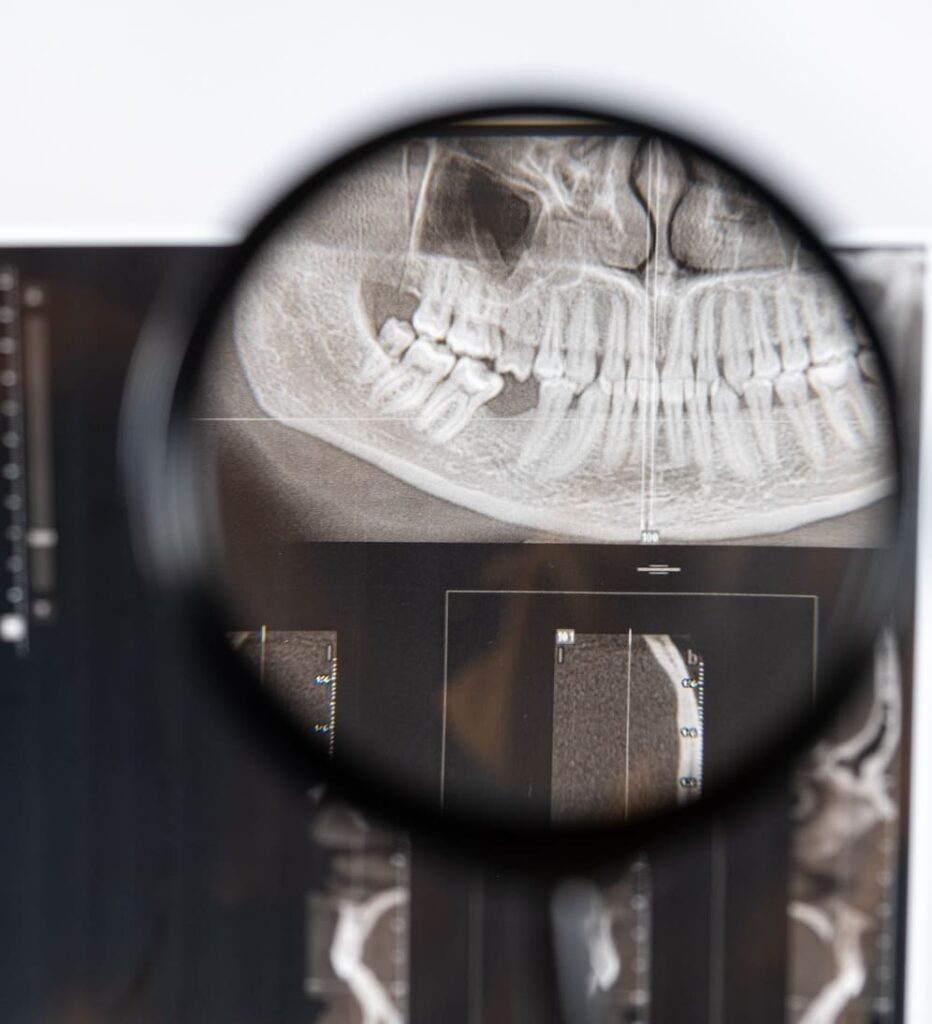

Temporomandibular Joint Disorder (TMJ) refers to a group of conditions affecting the jaw joint and surrounding muscles. The temporomandibular joint connects the jawbone to the skull, allowing movements such as talking, chewing, and yawning. When this joint becomes irritated or inflamed, it can lead to pain and discomfort, often radiating throughout the face, neck, and shoulders. One common but overlooked effect of TMJ is how it impacts your sleep. Jaw pain and muscle tension can make it difficult to relax at night, leading to restless sleep or even insomnia. Additionally, grinding or clenching your teeth while sleeping, a condition often associated with TMJ, can further disrupt sleep patterns.

Finding relief from TMJ often begins with choosing the right dental professional who specializes in treating this condition. Once you connect with a qualified dentist, they will likely fit you with a custom oral device designed to alleviate your symptoms. This device is worn during sleep and plays a key role in reducing the discomfort associated with TMJ.

By addressing these issues, the device provides much-needed relief to your temporomandibular joint. It reduces the strain on the jaw, allowing the joint to heal and minimizing symptoms such as jaw pain, headaches, and facial discomfort. This can lead to a significant improvement in both your daytime comfort and the quality of your sleep.